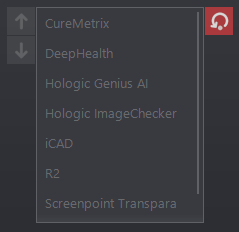

A nézegető támogatja a DeepHealth Saige-Density SR objektumokat, megjelenítve az eset sűrűségi pontszámát a CAD fejlécben és opcionálisan az átfedési adatokban az Emlőösszetétel információs címke használatával.

Kiegészítő információk jelennek meg az iCAD SR objektumokról, az esetpontszámot és az esetpontszám címkét is beleértve a CAD fejlécben. Ha szintetikus 2D képek és BTO sorozatok vannak jelen ugyanabban a vizsgálatban, a keresztkorreláció engedélyezve van, a felhasználó így a kiválasztott helyzetnek megfelelő tomo szeletre ugorhat. Végül az iCAD meszesedési csomókat (elforgatott négyzet) és tömegeket (ellipszis) ábrázoló grafikus ikonok frissítésre kerültek.

A DeepHealth CAD gyanúszintjeit a halmazvonalzóban található ikonban vannak feltüntetve. Egytől három sorig alacsony, közepes és magas gyanúszinteket jeleznek, ebben a sorrendben. Ha nincs vonal, az azt jelzi, hogy nincs gyanúszint meghatározva a CAD objektumban. Emellett ha a CAD objektum színt határoz meg a leletjelölőkre, a szín alkalmazásra kerül a képen és a halmazvonalzó grafikán. Ezt a funkciót az Opciók/Prezentációs állapotok/Mammográfiás CAD SR beállítási oldalon található Szín használata CAD jelölőkhöz beállításnál lehet letiltani.

A nézegető támogatja a ScreenPoint Transpara CAD objektumokat.

A Transpara logóval ellátott CAD fejléc tartalmazza a meszesedés és a tömegtalálatok számát, az algoritmus verzióját és a Transpara pontszámot (0 és 10 közötti egész érték).

A meszesedéseket gyémánt körvonal és az egyes meszesedések kontúrja jelöli.

A tömegeket a kontúrjuk jelöli (plusz az alapértelmezett marker, ha engedélyezve van).

A Screenpoint-hoz tartozik egy további lelettípus, a "döntéstámogatás", amely egy általánosabb vizsgálati területet ír le. Egyelőre a Transpara az egyetlen CAD, amely ezt a típust használja, de ez a jövőben változhat. Ahhoz, hogy az eszköz általánosabb legyen, a nézőke ezt a lelettípust "vizsgált területnek" (ROI) nevezi.

Mind a globális, mind a helyi CAD menübe új beállítási lehetőség került be az vizsgált területek megjelenítésére/elrejtésére. Az alapértelmezett a kikapcsolt állapot.

A Transpara esetében a vizsgált területek színkódolt körökként jelennek meg, amelyekhez általában - de nem mindig - pontszám is tartozik.

Lásd: ScreenPoint Transpara

A DeepHealth Saige-Q SR objektumok támogatásával bővült. A triázs fejlécében megjelenik az algoritmus neve és verziója, valamint az esetértékelés típusa és értéke.

További támogatás a Hologic Genius AI™ objektumaihoz.

A Genius AI™ érzékelés* (* FDA jóváhagyás függőben) olyan szoftvermodul, amely a lágyszöveti sűrűségként (tömegek, felépítési torzulások és aszimmetriák) vagy a meszesedési csomókként megjelenő gyanús emlőelváltozások mélytanulási neurális hálózatok segítségével történő azonosítására szolgál a Hologic Selenia Dimensions emlő-tomoszintézis képekben.

Lásd: Kereszt-korrelációs 2D CAD tomoszintézis képekben és CAD bizonyossági értékek

A DeepHealth frissített CAD objektumai támogatásának hozzáadása, amelyekben a 2D-s képeken megjelölt leletek egy adott BTO-kockában vagy képkockákon elfoglalt pozíciónak vannak megfeleltetve. Lásd: Kereszt-korrelációs 2D CAD tomoszintézis képekben